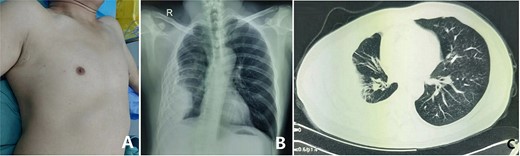

The patient is a 35-year-old male from western China. He suffered from pleuritis at the age of 17. Due to the incomplete treatment at that time, the pleuritis turned into empyema later. At the early stage, his chest wall was not deformed. From the age of 25, his right chest wall began to be depressed and scoliosis gradually appeared. During this period, he did not receive any effective treatment, and his condition gradually worsened. In half a year before admission, the patient often felt dyspnea, so he was admitted to our hospital for surgical treatment. The preoperative physical examination showed that the patient’s chest was asymmetric, the right side was largely depressed (Fig. 1A), the breath sound was low and the spine was scoliosis. Imaging examination showed that the right chest wall was depressed and shrunk, there were obvious lesions in the right thoracic cavity and the pleura was thickened (Fig. 1B and C). The patient was diagnosed as right empyema with right chest wall depression and scoliosis before operation. After full preparation, his operation was performed under general anesthesia. Left lateral decubitus position was adopted, and the right subaxillary longitudinal incision was performed. Subcutaneous and muscular tissues were dissected to expose the right ribs (Fig. 2A). After the ribs were cut in crisscross way, the thickened pleura was exposed (Fig. 2B). The pleura is stripped, and all lesions in the thoracic cavity were cleared. The thoracic cavity and surgical field were washed repeatedly, and then the chest wall was reconstructed with MatrixRIB. Firstly, the two ends of the cut rib were stretched as far as possible, and then MatrixRIB was used to extend and fix the two ends (Fig. 2C). Thoracic cavity and surgical field were washed again. After drainage tubes were retained, the incision was closed and the operation was completed (Fig. 3). There were no complications during the operation and the postoperative recovery was satisfactory. After operation, the right chest wall depression was basically eliminated, the chest wall was symmetrical on both sides and scoliosis was significantly reduced. The drainage tubes were pulled out 8 days after the operation. The incision healed well and the suture was removed 14 days after the operation. He was discharged 15 days postoperatively without any complaint.

(A) Preoperative chest wall appearance; (B) X-ray examination and (C) computed tomography examination.